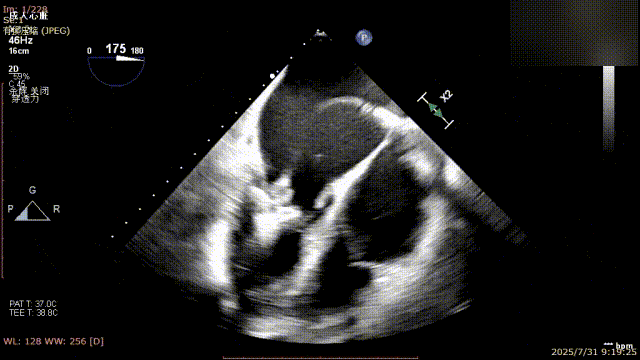

手术过程中,麻醉与围术期医学科副主任医师马金本确保麻醉过程平稳。心脏大血管外科主治医师董明亮穿刺股静脉置入血管鞘,并在心脏超声科梁皓主任及段福建教授TEE引导下,顺利穿刺房间隔,房间隔穿刺高度4.9cm。随后,在王安彪主任以及刘洋教授指导、心脏超声科梁皓主任TEE引导下,董明亮医师沿输送系统将延展呈“一字型”状态的国产夹合器送至左房,缓慢关闭夹合器并进行弹道测试。调整夹合器位置和方向后,董明亮医师再次将夹合器延展呈“一字型”完成跨瓣,避免发生腱索缠绕,成功捕获瓣叶后关闭夹合器,二尖瓣反流显著下降。夹合器完全解离后,超声示二尖瓣反流程度显著下降,残余反流0,平均跨瓣压差1mmHg,手术圆满成功。

房间隔穿刺

夹合器“一字型”状态进入左房

缓慢关闭夹合器